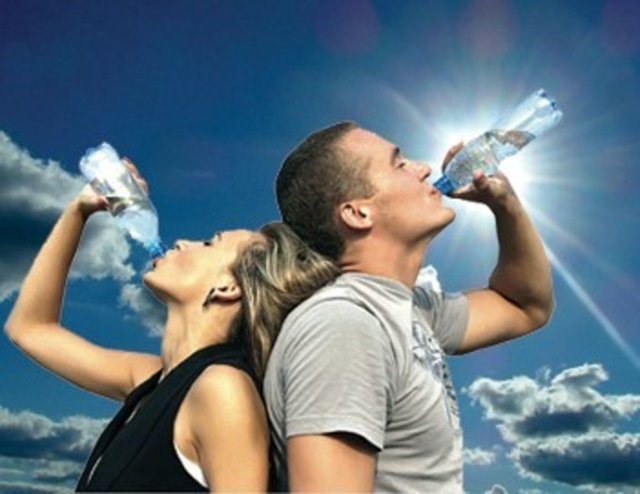

Bugünlerde bol su içmek her zamankinden çok daha fazla önem taşıyor. Hele de beyin sağlığı açısından